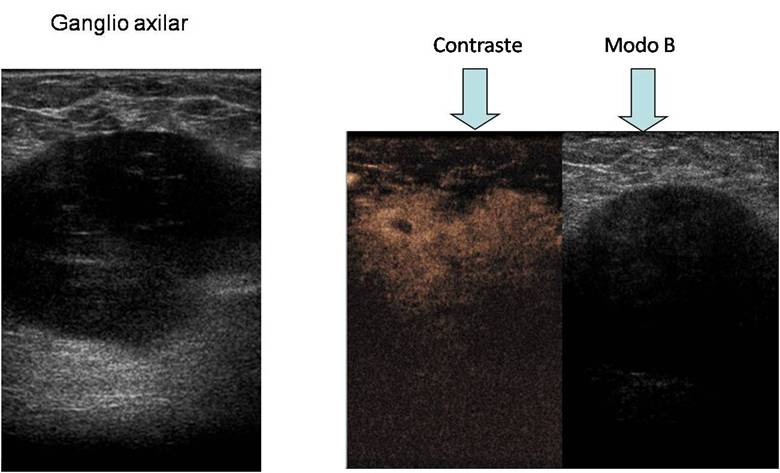

Valoració ecogrà fica dels ganglis axil·lars i nòduls mamaris que s'ajuda d'un contrast ecogrà fic: La zona no contrastada és la zona sospitosa.